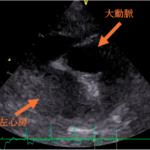

⾼度画像診断

当院ではCT‧MRIをはじめ、最新の画像診断設備を整えています。撮影および読影の際には画像診断専⾨医と連携することでより正確な診断へと導きます。